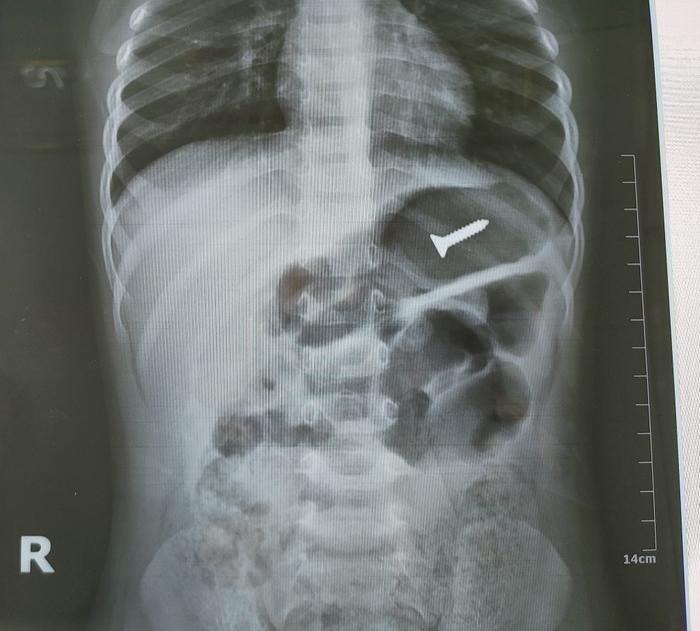

14/05/2023 15:52Bé 3 tuổi nuốt nhập viện khẩn vì nuốt nhầm thứ đồ nhà nào cũng có, bác sĩ cảnh báo cực kỳ nguy hiểm

Mới đây, Bệnh viện đa khoa tỉnh Tuyên Quang tiếp nhận bệnh nhi N.T.Đ. 32 tháng tuổi, trú tại huyện Hàm Yên, tỉnh Tuyên Quang được chẩn đoán dị vật đường tiêu hóa.

Theo gia đình, trước khi nhập viện khoảng 2h, người thân phát hiện trẻ nhỏ ở nhà hiếu động đã nuốt nhầm đinh ốc vít, sau đó đau bụng từng cơn, quấy khóc, buồn nôn…

Ngay sau đó, người thân đã đưa trẻ đến Bệnh viện đa khoa tỉnh Tuyên Quang để thăm khám. Kết quả chụp X-Quang cho thấy có 1 di vật cản quang trong ống tiêu hóa cao, các cơ quan khác chưa phát hiện bất thường.

Bệnh nhân được điều trị, chăm sóc, theo dõi sát tình trạng bụng tại khoa Ngoại Tổng hợp của Bệnh viện và chụp phim X-Quang nhiều lần theo dõi sự di chuyển của chiếc đinh ốc đề phòng các biến chứng thủng ruột nếu sảy ra sẽ được phẫu thuật cấp cứu ngay.

Rất may mắn là sau 3 ngày, bệnh nhi đại tiện được ra chiếc đinh vít nên đã được xuất viện.